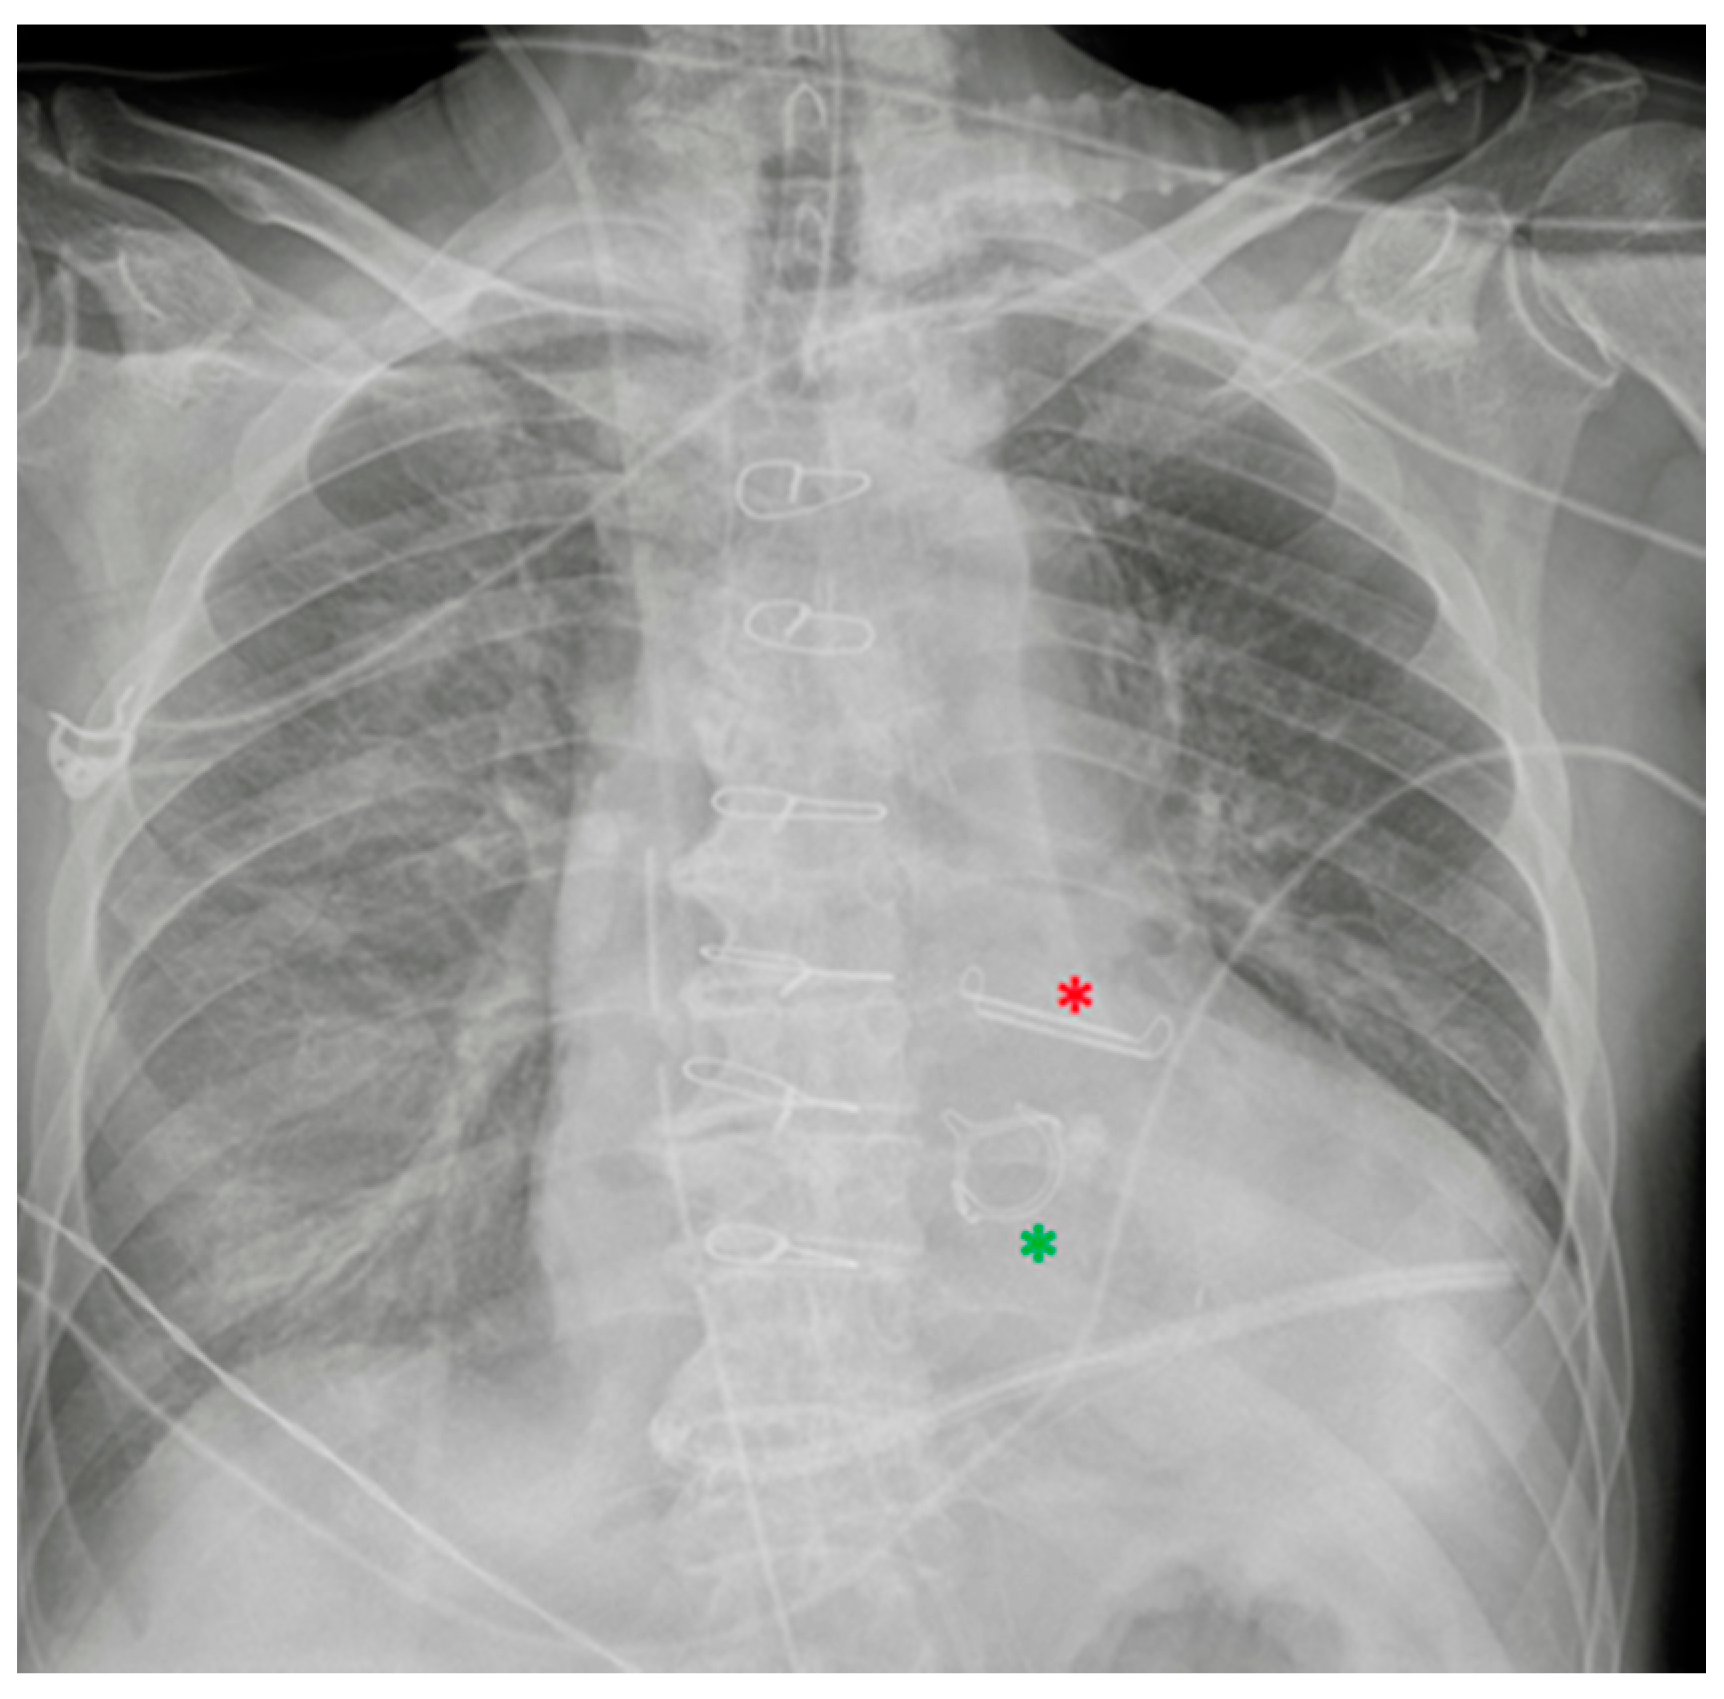

6.1. Nasogastric Tubes

| Nasogastric tubes | Proximal (oesophagus)/distal (duodenum) * misposition Coiling/kinking Insertion into the respiratory tree → aspiration pneumonia Gastric wall perforation Intracranial insertion (rare) * |